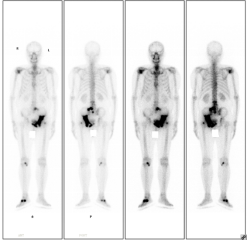

患者老年男性,因前列腺癌骨转移伴明显疼痛,于20228月行全身骨显像,后给予锶89及唑来膦酸等联合治疗,疼痛明显缓解,于20235月行全身骨显像复查,病灶明显减少、范围缩小、病灶活跃程度减低。